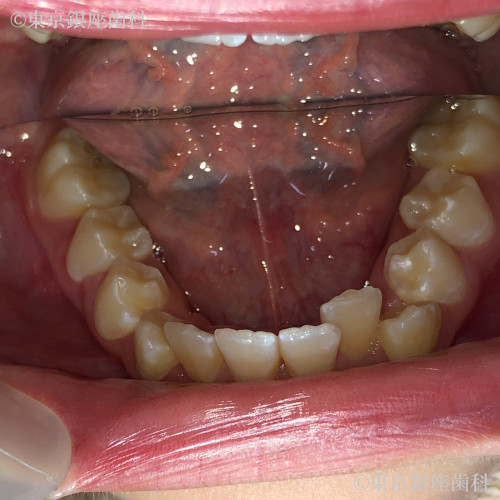

After

10代 女性

疾患 矯正

施術内容 矯正

治療期間 11ヶ月 費用 65万円(税込)

インビザライン:ファースト